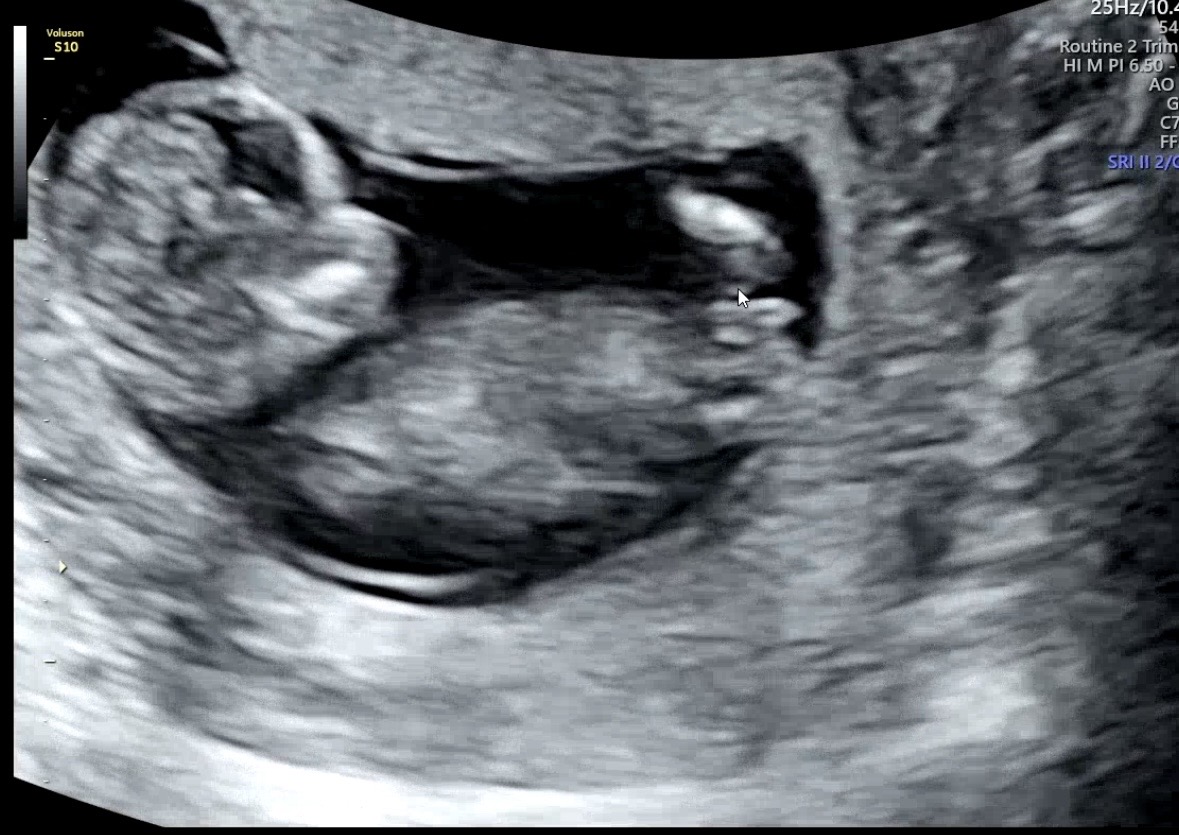

각도법 투표 부탁드려요!

성별 어떻게 보이시나요?!